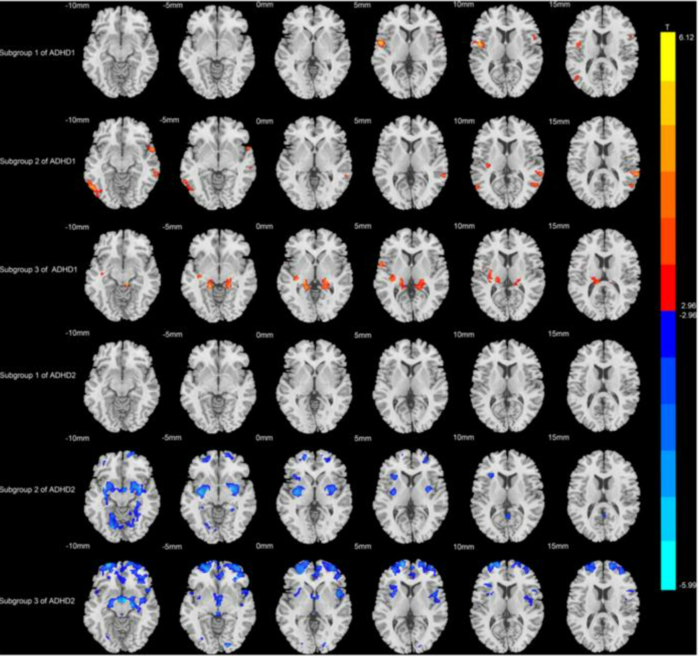

하위 유형 1: 주의력 관련 영역 변화실제로 분석 결과, 뇌 변화 패턴과 행동 증상이 뚜렷하게 구분되는 두 가지 ADHD 하위 유형이 확인되었다. 첫 번째 유형은 주로 주의력 문제와 관련이 있다. 이 그룹의 ADHD 환자들은 특히 전두엽과 소뇌에서 회백질 부피가 증가한 것으로 나타났다.

이러한 뇌 영역은 주의력, 계획, 협응력 등 여러 기능에 중요한 역할을 한다. 주의력 문제가 심할수록 뇌의 이러한 변화가 더욱 두드러지게 나타났다. 이는 일부 ADHD 아동의 경우 주의력에 중요한 뇌 네트워크 발달에 특히 문제가 있음을 시사한다.

| ▲ MRI 스캔 결과, 두 가지 ADHD 하위 유형에서 회백질의 변화가 다르게 나타났다. 한 유형에서는 회백질 부피가 증가하고(빨간색), 다른 유형에서는 감소한다(파란색). © Tianzheng Zhong, Feng Wang, Jianfeng Qiu, Weizhao Lu. CC BY-NC |

하위 유형 2: 해마 및 소뇌 변화두 번째 하위 유형은 다른 양상을 보였다. 이 그룹의 ADHD 환자들은 여러 뇌 영역에서 회백질 부피가 감소한 것으로 나타났다. 중 박사 연구팀이 관찰한 바와 같이, 증상이 심할수록 이러한 기능 저하는 더욱 두드러졌다. 특히 소뇌와 해마가 큰 영향을 받았는데, 이 부위들은 운동, 감정, 기억, 동기 부여 등을 담당하는 영역이다.

이는 이 아형이 단일 증상으로 특징지어지는 것이 아니라 여러 행동 영역에 영향을 미친다는 사실과 일치한다. 영향을 받은 사람들은 일반적으로 주의력 결핍과 과잉 행동 또는 충동적인 행동을 모두 보인다.

새로운 분석 방법을 사용해 두 가지 하위 유형이 뇌 변화와 행동 증상 간의 관계에서 차이를 보인다는 사실이 밝혀졌다. 한 하위 유형에서는 주의력 네트워크가 특히 중요한 역할을 하는 반면, 다른 하위 유형에서는 뇌 전체에 걸쳐 더 광범위하게 분포된 시스템이 관여하는 것으로 나타났다.